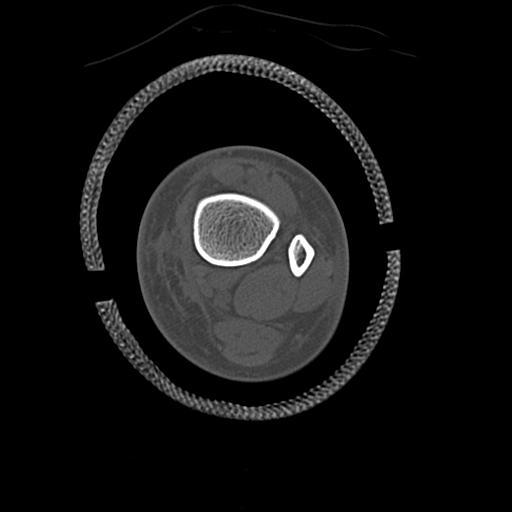

49554 3/13 膝 4R 3/16 4R 1/18 2R 78歳男性 膝蓋骨骨折